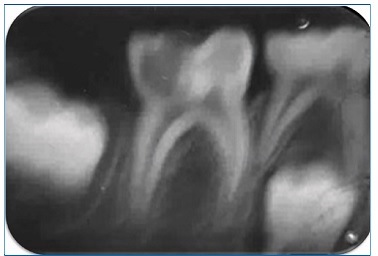

Intraoral examination revealed the presence of gingival hyperplasia in the upper arch and gingivitis associated with the presence of dental biofilm, arched palate, Angle class I occlusion without crossbite or open bite, dolichofacial pattern, labial hypotonia, and mild enamel hypomineralization (presence of whitish-cream demarcated opacities)14 in the permanent maxillary central incisors (Figures 4 and 5). Moreover, she had caries lesions in the deciduous mandibular left second molar and mandibular first permanent molar, which presented great coronary destruction and pulp involvement (Figures 6 and 7).

No demarcated opacities, enamel breakdown, or atypical restorations were observed in the patient’s other first permanent molars. Still, the tooth extraction might have been due to molar incisor hypomineralization (MIH), based on the judgment criteria for MIH diagnosis proposed for prevalence studies, where one of the criteria to diagnose “Suspected for extraction due to MIH” is the absence of the first permanent molars in a sound dentition in combination with demarcated opacities on the incisors.15 Periapical radiography of the affected teeth was performed. Bitewing radiographs were impossible to make due to the patient’s uncooperative behavior and reduced mouth opening.